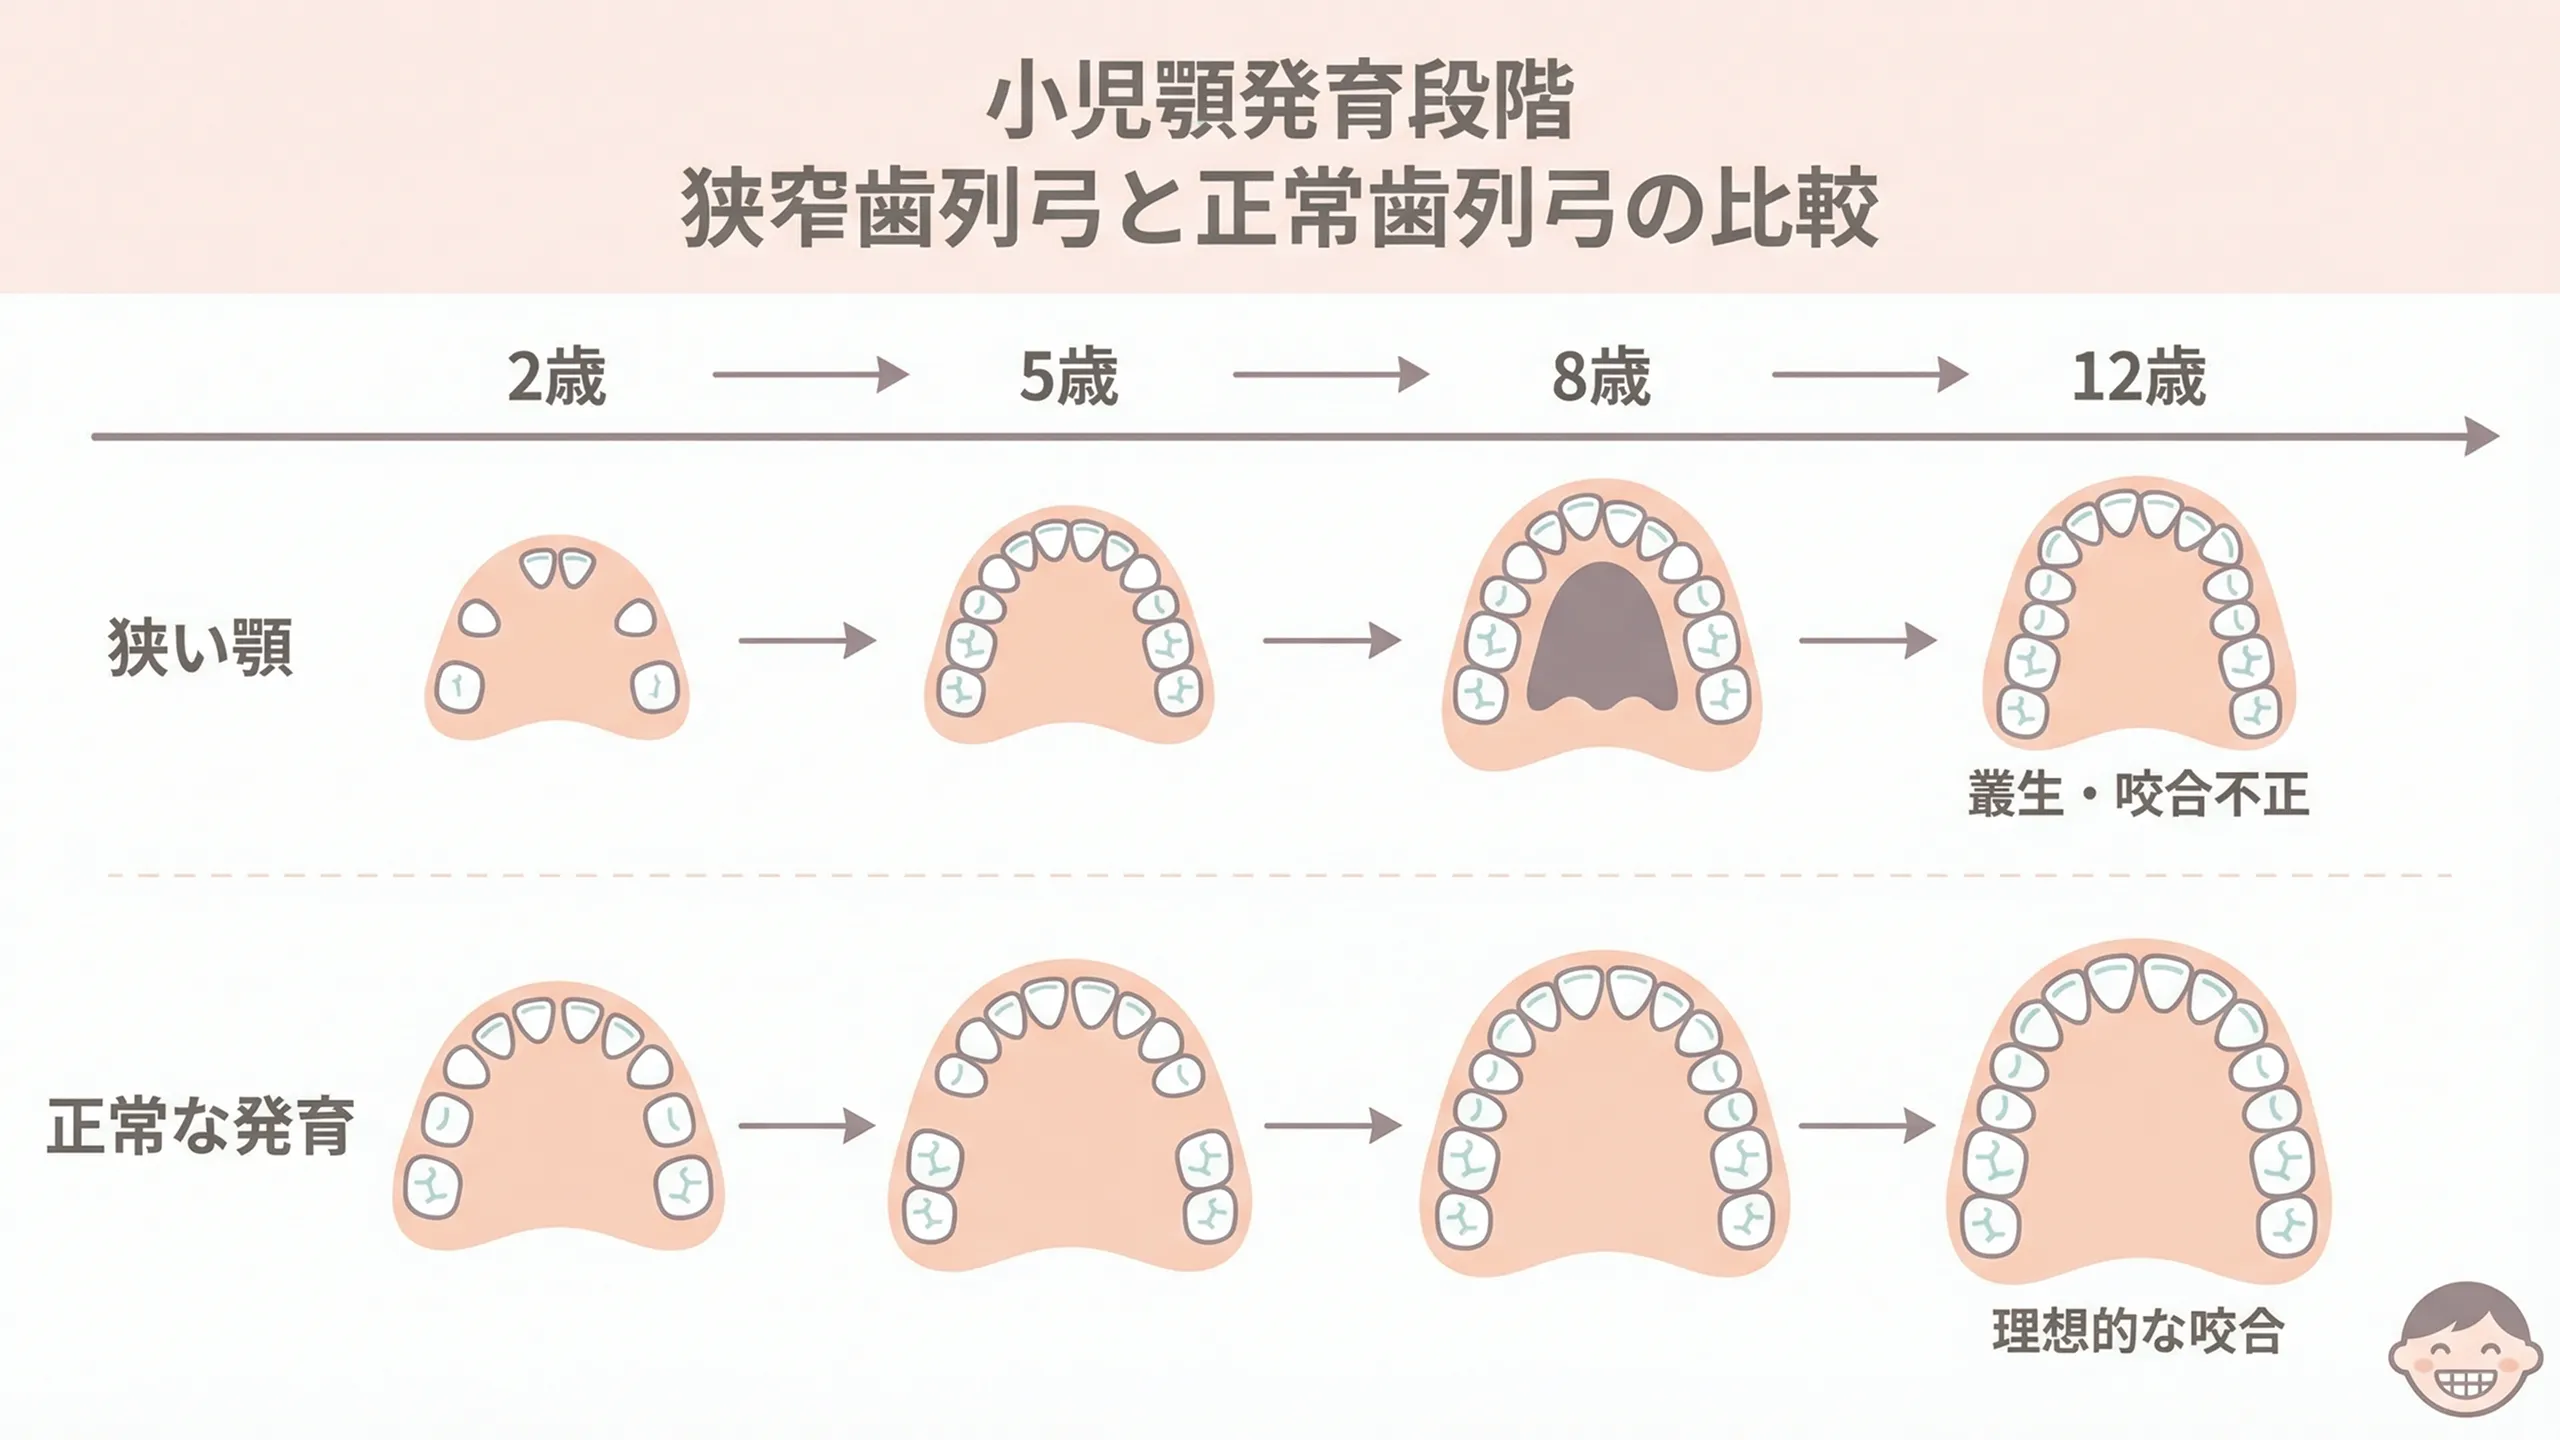

1. あごの健やかな成長を促せる

あごの幅や前後のバランスを整えることで、永久歯が並ぶための「スペース」を確保できます。

1. あごの健やかな成長を促せる

あごの幅や前後のバランスを整えることで、永久歯が並ぶための「スペース」を確保できます。これにより、歯が重なって生える叢生(そうせい)や、かみ合わせのズレ(交叉咬合:こうさこうごう)を予防・改善しやすくなります。

特に上あごの幅が狭いタイプは、早めに拡大治療を行うことで、上下のズレを直しやすくなり、顔の左右差が悪化するのを防ぐこともできます。成長期に土台を整えておくことで、大人になってから外科的な治療が必要になるリスクを減らせます。